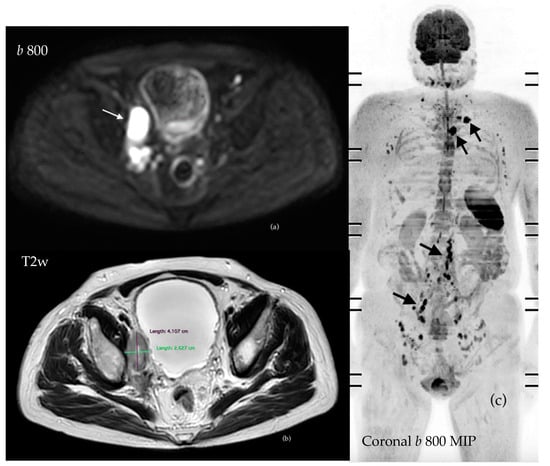

3.4.2. Assessment of Nodal Disease

3.4.3. Assessment of Visceral Disease